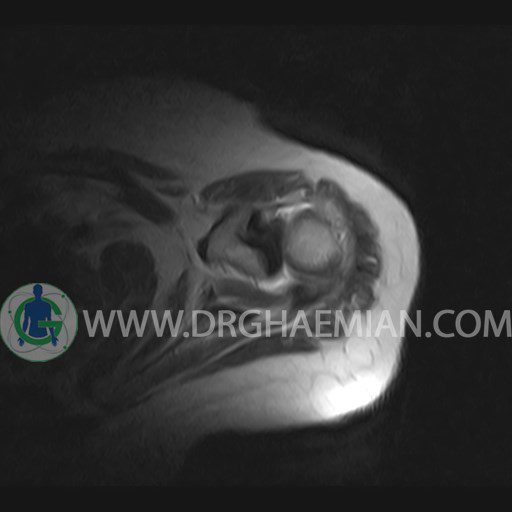

ام آر آی آتروفی عضلانی کتف بیمار

ام ار آی کتف یک روش تصویربرداری است که به وسیله آهنرباهای قدرتمند از قسمت کتف تصاویری ایجاد می کند. این نوع تصویربرداری از تشعشعات استفاده نمی کند. در این کیس آتروفی عضلانی کتف به همراه پارگی تاندون بالاخاری، بورسیت ساب دلتوئید و افیوژن مفصل دیده می شود.

– Complete tearing of supraspinatus tendon with grade 2 retraction and muscle atrophy

– AC joint hypertrophy with subacromial – subdeltoid bursitis

– Glenohumeral joint effusion

are seen.